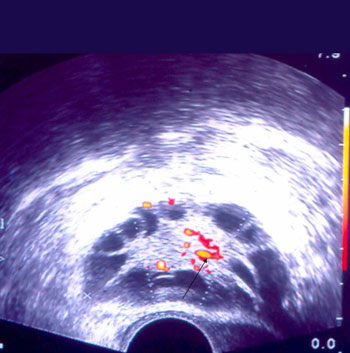

Πρόσφατες in vivo και in vitro μελέτες, υποστηρίζουν το σημαντικό ρόλο της συνεχούς

υψηλής ή αυξανόμενης ροής αίματος στο ωοθυλάκιο, κατά τη διάρκεια της ωοθυλακιογενεσίας.(1)

Η αιματική αυτή ροή εξασφαλίζεται μέσω μικρών αγγείων, τα οποία πορεύονται κατά

μήκος της εσωτερικής επιφάνειας της θήκης του ωοθυλακίου(2) (εικόνες 1, 2).

Εικόνα 1. Νεόπλαστα αγγεία

στο τοίχωμα ωοθυλακίου.